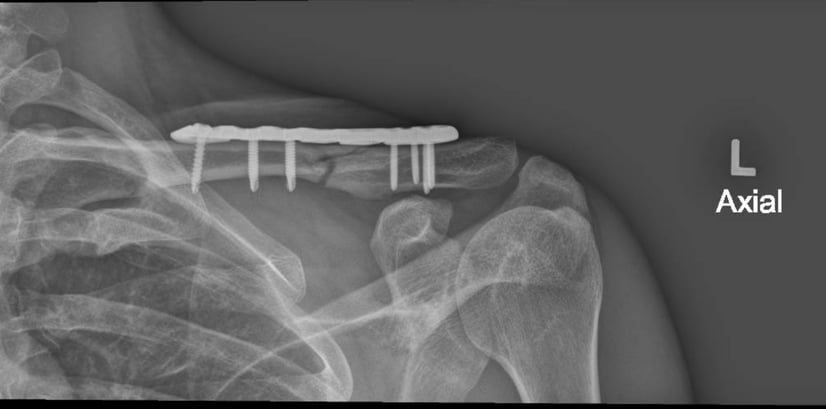

Internal Fixation: This involves using screws, plates, or pins to hold the bones together. The surgeon will make a small incision and carefully position the hardware to stabilise the bone.

Good healing of a fracture after surgical fixation with a plate and screws.